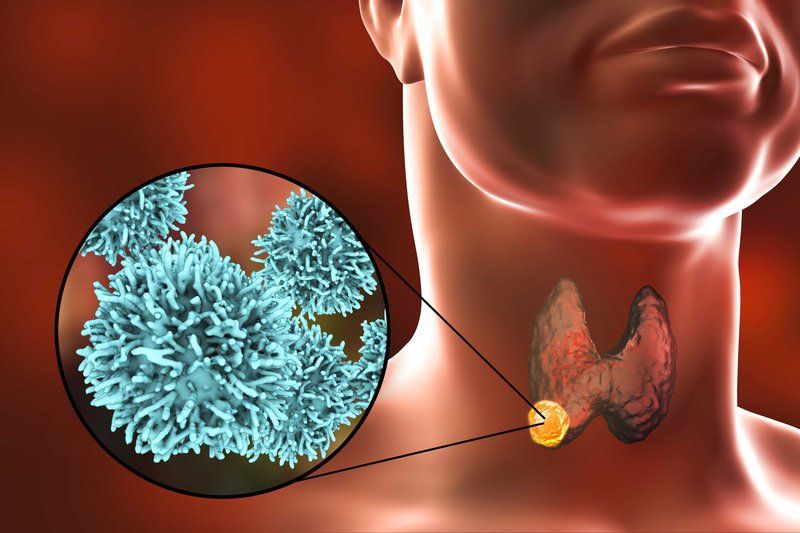

Viêm màng não do nấm và những nguyên nhân khác như ký sinh trùng là trường hợp hiếm gặp hơn. Đây là ình trạng viêm màng não nhưng không bị nhiễm trùng. Nguyên nhân của thể bệnh này có thể là chấn thương đầu, phẫu thuật não, bệnhLupus ban đỏ, ung thư hay sử dụng một số loại thuốc nhất định.